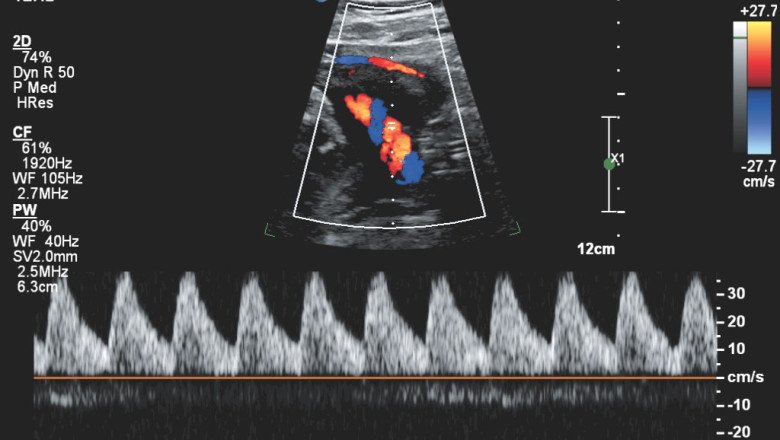

Doppler Ultrasound is a medical imaging technique that uses sound waves to create images of the body’s internal structures. The technique is based on the Doppler effect, which describes the change in frequency of a sound wave when it is reflected off a moving object. In this article, we will discuss the roles of Doppler ultrasound in various medical applications.

Doppler Ultrasound plays a critical role in the diagnosis and management of cardiovascular diseases. It is used to measure blood flow velocity and direction in the heart and blood vessels. This information can be used to assess the function of the heart valves, detect blockages in the blood vessels, and evaluate the severity of heart disease.